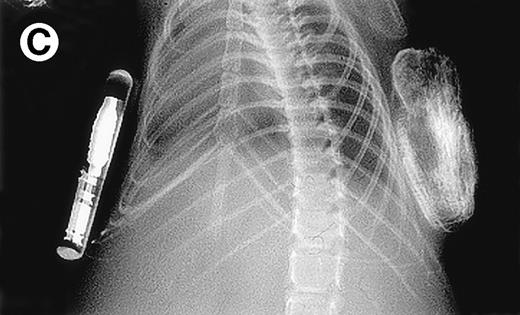

Growth of myeloma blood cells from patient no. 10 in SCID-hu host. SCID-hu host was inoculated with blood cells (containing 0.1% plasma cells) and with PC-depleted blood cells. (A) Human Ig levels. (•) Blood cells; (○) PC-depleted blood cells; (▪) host inoculated with bone marrow cells containing 11% myeloma plasma cells. (B) Flow cytometry dot plot of CD38CD45 profile of the blood cells. The sort window excluding CD45− and CD45+plasma cells is shown. (C and D) X-radiograms of host injected with blood cells (C) and with PC-depleted blood cells (D). Note severe decalcification of myelomatous human bone in (C).